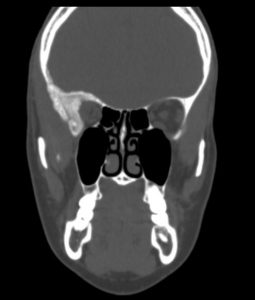

Ασθενής γυναίκα, 41 ετών με εξόφθαλμο δεξιά.

H Μαγνητική & Αξονική Τομογραφία εγκεφάλου ανέδειξε χωροκατακτητική εξεργασία στην περιοχή της πτέρυγας του σφηνοειδούς οστού, δηλ. του άνω (οροφή) και του πλαγίου τοιχώματος του οφθαλμικού κόγχου. Η εξεργασία επεκτείνονταν κατά μήκος της σκληράς μήνιγγας ενώ στην περιοχή του κροταφικού πόλου παρουσίασε ενδοκρανιακή επέκταση. Η πάχυνση του οστού του κόγχου προκαλούσε πίεση των περιεχομένων του κόγχου με αποτέλεσμα εξόφθαλμο.